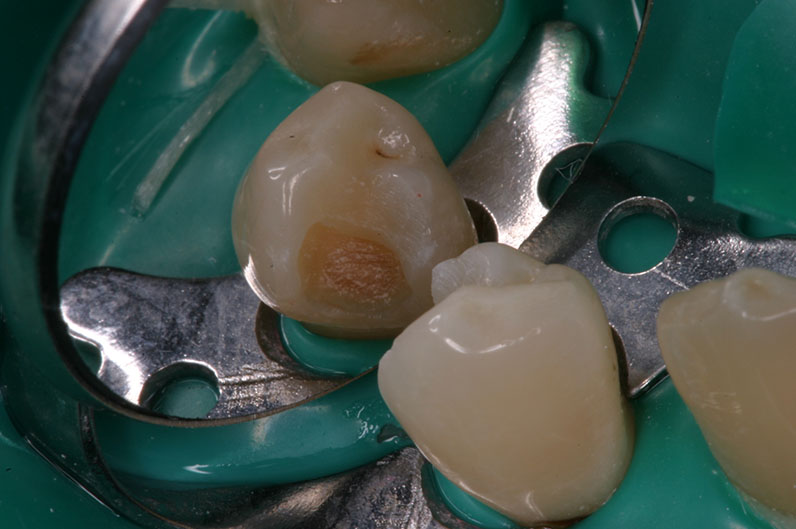

Преди екскавиране

с Proface*

След екскавиране